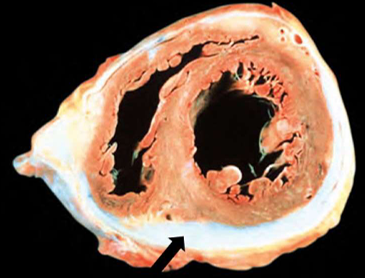

Hypertrophic Cardiomyopathy

asymmetric septal hypertrophy, septal muscle bulges into the left ventricular outflow tract, "banana-shaped" ventricular lumen